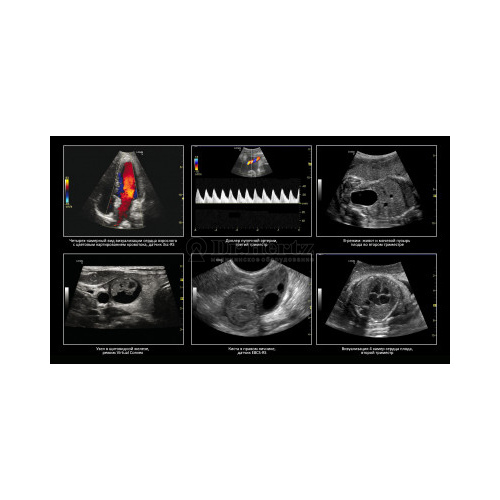

Ваши обязательства перед пациентами и удобство ультразвуковой визуализации идут рука об руку на пути к здоровому обществу. Система LOGIQ V5* делает передовые ультразвуковые технологии простыми и доступными для пользователей и позволяет проводить целый ряд исследований органов брюшной полости, сердца, проводить акушерские исследования и прочие виды диагностики.

Проводите современные диагностические исследования, позволяющие получать достоверные результаты в самых разных областях:

• Передовые режимы визуализации, например ЦДК, импульсно-волновой и энергетический доплер (ЭДК), позволяют измерять параметры кровотока на определенном участке при проведении диагностики и мониторинга.

• Анатомический М-режим дает возможность оценки области интереса в произвольной плоскости.

• SonoBiometry представляет собой рабочий инструмент для автоматизации и быстрого проведения основных измерений биометрии плода.